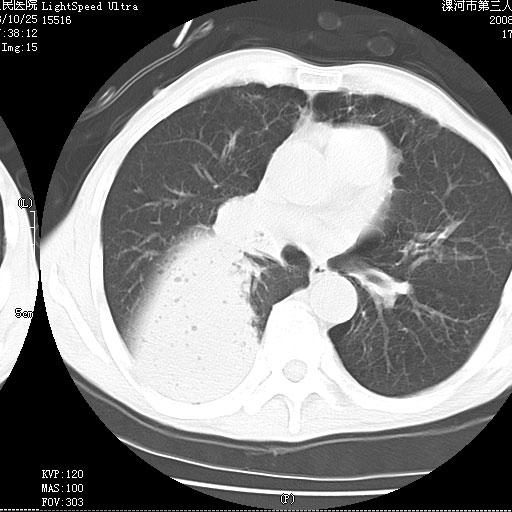

考虑为右肺下叶支气管痰栓形成并阻塞性肺不张及肺炎。

病变按肺叶分布,病变内可见多个小空腔影,未见充气支气管影,中间段支气管管腔肺窗示密度欠均匀,下肺支气管分叉处基底段支气管隐约可见,未见明显狭窄,中叶支气管通畅,

考虑:阻塞性肺炎伴小脓肿形成可能性大。(痰栓可能性大)

右下肺实变,内有弥漫分面小气泡而无支气管征,叶间裂前移,呈臌大之形,而无收缩之状,兼纵隔稍左行移,故。不支持不张,倒支持大叶肺叶,如楼上所说,小气泡不象残留之肺,不可以考虑产气菌感染吗。

阻塞性肺炎,肺脓肿形成。依据,右下支气管不通,大片实变形内可见小气泡。不支持肺不张。